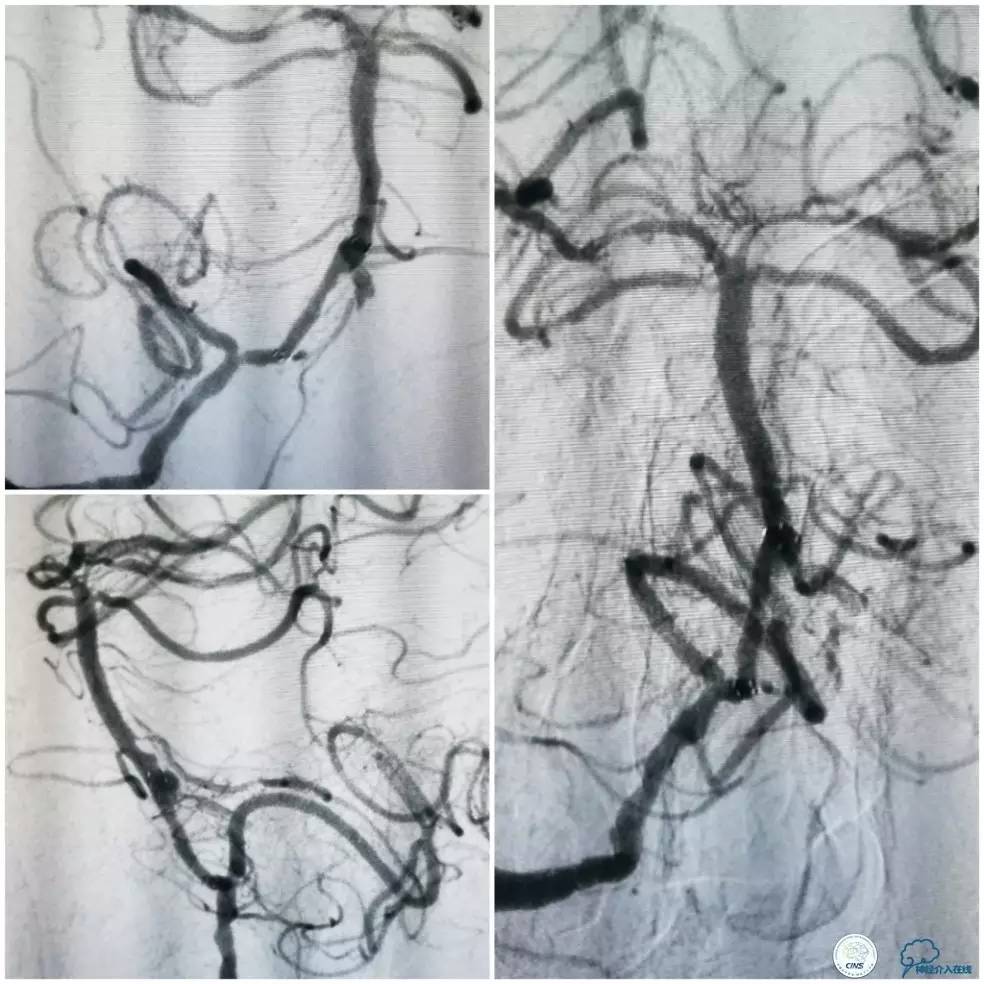

Transend(0.014″300cm)微导丝+Echelon-10微导管,小心通过右椎动脉V4段病变后置于右大脑后动脉P1段(图13)。

图13

Gateway球囊(1.5mm×15mm)于狭窄段扩张后放置Wingspan支架(2.5 mm×15mm),撤出微导丝后造影,局部狭窄率50%,支架内中远段见细小充盈缺损,考虑急性血栓形成,予以欣维宁5ml动脉内缓慢注射未见好转(图14)。

图14

遂再次将Transend微导丝送至右大脑后动脉P1段,使用Gateway球囊(2.0mm×15mm)于支架最狭窄处后扩张(图15)。

图15

其后造影显示支架贴壁良好,远端血管显影好,前向血流TICI3级(图16)。

图16